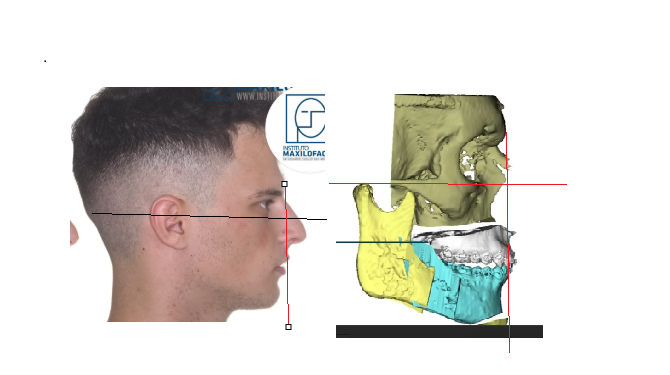

Lets start with gustavo, Alfaro bimax case, the most famous bimax result online:

lets look at his skeleton, which explains the huge transformation:

Lets start with gustavo, Alfaro bimax case, the most famous bimax result online:

lets look at his skeleton, which explains the huge transformation: